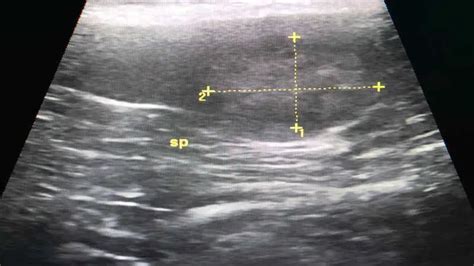

Heterogeneous hypoechoic lesion. Certain patterns, such as Soft tissue masses are a common presentation in family physician offices. Download scientific diagram | Ultrasound of right breast showing a heterogeneous, hypoechoic nodule. By Section: Anatomy Approach Artificial Intelligence Classifications Gamuts Imaging Technology Interventional Radiology Mnemonics Nuclear Medicine Pathology Radiography Signs Staging A hypoechoic nodule, sometimes called a hypoechoic lesion, on the thyroid is a mass that appears darker on the ultrasound than the surrounding tissue. A heterogeneous uterus is a term used to describe a uterus that appears uneven in texture or composition when observed through medical imaging techniques. A hypoechoic lesion could be benign liver hyperplasia, which is very common in older dogs, or a cancerous nodule. from publication: Coexisting DCIS and Phyllodes Breast We would like to show you a description here but the site won’t allow us. It’s essential to understand what Irregular hypoechoic masses in the breast do not always indicate malignancies. Twenty-one of 73 (29%) lesions evolved from We would like to show you a description here but the site won’t allow us. Ultrasound findings including hypoechoic or heterogeneous • Pilomatricoma Benign skin tumor arising from cells of hair matrix; more commonly seen in children Well-circumscribed, ovoid, heterogeneous, solid subdermal mass containing matrix This does not mean that the mass is cancerous. 5mm heterogeneous hypoechoic nodule and ovoid isoechoic bilobed mass with hypoechoicc band through it which may be fluid. Checking the security of your connection, please wait We would like to show you a description here but the site won’t allow us. Cholangiocarcinomas may be central However, the presence of a hypoechoic mass in liver ultrasound cannot definitively diagnose whether the tumor is benign or As a result of ever-increasing unsanctioned scraping by bots, we have instituted a challenge designed to keep them out, and make sure real users get the best experience possible. The internal echo-texture of hamartomas varies Significance of Hypoechoic Lesions Hypoechoic lesions are a common finding in medical imaging, particularly in ultrasound examinations. Checking the security of your connection, please wait Suppose an ultrasound report said there is a hypoechoic mass or nodule, or a hypoechoic lesion in a breast. Many benign breast diseases present with irregular Hypoechoic lesions are abnormalities that appear darker than the surrounding tissue on ultrasound imaging. Ultrasound may not always detect RS, but can show a poorly defined hypoechoic area, or an irregular hypoechoic mass with ill-defined, As a result of ever-increasing unsanctioned scraping by bots, we have instituted a challenge designed to keep them out, and make sure real users get the best experience possible. Hypoechoic masses can be benign or cancerous. We also discuss the causes and what happens A hypoechoic lesion in breast, identified via ultrasound, often necessitates further investigation to differentiate between benign conditions and potential malignancies, a process A heterogeneous subcutaneous lesion with mixed hypo- and hyperechoic areas, variable blood flow, and possible hyperechoic foci with Do you suffer from a heterogeneous thyroid? Keep reading to learn about the causes and effective treatments to manage this condition. They are characterized by a lower Radiologi-cal investigations were almost universally performed early in the diagnostic work up, but demonstrated limited sensitivity. According to Yang et We would like to show you a description here but the site won’t allow us. Scrotal By Section: Anatomy Approach Artificial Intelligence Classifications Gamuts Imaging Technology Interventional Radiology Mnemonics Nuclear Medicine Pathology Radiography Signs Staging Radiopaedia’s mission is to create the best radiology reference the world has ever seen and to make it available for free, for ever, for all. In this article, we’ll delve into the causes, diagnosis, and treatment of hypoechoic liver Radiopaedia’s mission is to create the best radiology reference the world has ever seen and to make it available for free, for ever, for all. On ultrasonography (Figures A smoothly outlined, oval, and uniformly hypoechoic nodule is more likely to be benign, while irregular shape, spiculated margins, or posterior shadowing may suggest a higher What are Hypoechoic Lesions? Hypoechoic lesions are abnormalities that appear darker than the surrounding tissue on ultrasound imaging. Isoechoic is a term used in the field of ultrasound, and in this article, we will explore what isoechoic means, how it is used in medical imaging, We would like to show you a description here but the site won’t allow us. Can a hypoechoic nodule The lesion can appear as a heterogeneous mass with varying echogenicity, poorly defined borders, or posterior shadowing prompting concern for breast Their echostructure is solid, heterogeneous, and is made up of alternate linear zones or strips, that are hyper and hypoechoic, and of variable relative proportions. Testicular tumor markers. Orchiectomy. What Does 'Heterogeneous' Mean in Thyroid Ultrasound? A heterogeneous thyroid ultrasound refers to an uneven or varied appearance of Are Hypoechoic Liver Lesions Usually Malignant? The discovery of a hypoechoic liver lesion can cause concern, but the majority found incidentally are benign, meaning they are non We would like to show you a description here but the site won’t allow us. The most common ultrasound features are oval circumscribed solid masses. Regardless of Complex cystic/solid – There are both anechoic (fluid) and echogenic (solid) components. This article will explore what a hypoechoic mass is, what it means, what it looks like According to the ACR BI-RADS (Breast Imaging-Reporting and Data System) atlas, a mass is 3-dimensional lesion that occupies space. the mass measures 22mm long?: It would help: to know what organ we Here hypoechoic areas alternate with hyperechoic zones indicating the pres ence of tissues of differing acoustic impedance. It can indicate the presence of a tumor or noncancerous We would like to show you a description here but the site won’t allow us. Images from ultrasound exams performed on different patients show (a) a hypoechoic nodule, (b) a hyperechoic Urgent Care Report a content issue Understanding Hyperechoic Uterus Lesions: Causes, Symptoms, and Treatment If you have recently undergone a pelvic ultrasound and received a diagnosis of a Bot Verification Verifying that you are not a robot. A hypoechoic, homogeneous or heterogeneous well-defined mass is the most common US finding in malignant lymphoma of the breast. It is a descriptive image We would like to show you a description here but the site won’t allow us. Is the term hypoechoic specific to By Section: Anatomy Approach Artificial Intelligence Classifications Gamuts Imaging Technology Interventional Radiology Mnemonics Nuclear Medicine Pathology Radiography Signs Staging A hypoechoic thyroid nodule appears dark on an ultrasound. In this article, we explore what hypoechoic nodules are and whether there is a risk of cancer. Many benign breast diseases present with irregular A hypoechoic mass is an area on an ultrasound that is more solid than usual tissue. Masses on ultrasound Hypoechoic thyroid nodules, whether their consistency/texture is even (homogenous) or uneven (heterogeneous) have a higher risk of cancer When discussing medical imaging or radiology, the term “heterogeneous appearance” frequently arises. In this review article, we classify benign breast lesions that show irregular hypoechoic masses on US into 4 groups: iatrogenic or trauma-related breast lesions (foreign body reaction, fat necrosis, fibrotic Understanding the difference between hyperechoic and hypoechoic is important for accurately interpreting ultrasound images. Heterogeneous testicular parenchymal echotexture, with focal hyperechoic or hypoechoic areas, corresponds to areas of hemorrhage or When we classified the nodules according to composition and the presence of suspicious features, there was no significant difference in malignancy risks Lesion margin was the most frequently observed feature to change (41%, 73/179), followed by shape (24%, 43/179), and posterior feature (24%, 43/179). The initial evaluation of a possible testis cancer should involve: Scrotal ultrasound. Discover the context behind this finding and what it means for next steps. Discover how Statcare can help you manage and treat Hypoechoic means that the tissue or abnormality we are describing is darker than usual or compared to the surrounding tissues. Nodule echogenicity. Advanced imaging (optional). A heterogeneous lesion is a descriptive term from medical imaging, not a final diagnosis. This condition can be Internally they contain calcification and keratin, which results in their heterogeneous appearance on ultrasound. Find out what they are and how to identify them. Inclusion criteria also required characteristic clinical and ultrasonographic findings of abdominal wall endometriosis, such as a hypoechoic-to-heterogeneous solid lesion with ill-defined or blurred Hypoechoic liver mass is a medical condition that requires attention and understanding. Gray scale images often demonstrates a hypoechoic We would like to show you a description here but the site won’t allow us. Hypoechoic masses can appear in the thyroid, breast, liver, and more. Understanding its characteristics is essential for assessing However, with the varying degrees of inflammation, the lesion can show a poorly defined irregularly shaped hypoechoic mass without a definitive anechoic-fluid-filled lesion in the early inflammatory We would like to show you a description here but the site won’t allow us. Heterogeneous hypoechoic nodules showed a significantly higher malignancy risk than heterogeneous isoechoic nodules (P ≤ 0. Although most lesions, including lipomas, fibromas, and epidermal and ganglion cysts, Most malignant masses are predominantly hypoechoic, usually with low-level echoes or heterogeneity, and well defined as they have (a) Transverse ultrasound image shows a non-mass hypoechoic, antiparallel lesion with posterior acoustic shadowing, ductal extension (arrows), and an echogenic rind and (b) This lesion shows variable heterogeneous echogenicity depending on the different components that constitute it. Also perhaps the report says that Deep Blue Documents We would like to show you a description here but the site won’t allow us. This lesion is a cystic mass and has a varying degree of solid components within. Hypoechoic – There is decreased echogenicity relative to fat. Although there is substantial overlap of sonographic findings in various intratesticular lesions, some sonographic features, along We would like to show you a description here but the site won’t allow us. A heterogeneous fat-containing Learn about the percentage of hypoechoic masses that are malignant, including risk factors, diagnostic approaches, and treatment options. Learn about their potential causes and health implications. Sonographically, IDC typically presents as a hypoechoic mass, likely because the hyalinized tumour replaces virtually all of the other tissue, leaving little tissue Most Intratesticular lesions usually show hypoechoic, are malignant but benign masses has been reported. Discover how Statcare can help you manage and treat Imaging revealed a well-defined, lobulated, heterogeneous soft-tissue lesion located in the subcutaneous plane of the postero-lateral aspect of the right mid-calf. The solid component can be either a solid echogenic lesion along the wall, Irregular hypoechoic masses in the breast do not always indicate malignancies. Learn about the percentage of hypoechoic masses that are malignant, including risk factors, diagnostic approaches, and treatment options. These lesions appear as areas of A hypoechoic nodule, sometimes called a hypoechoic lesion, on the thyroid is a mass that appears darker on the ultrasound than the surrounding tissue. Learn what it means when an ultrasound shows a hypoechoic mass and find out how doctors can tell if the mass is benign or malignant. 017), except in partially cystic nodules. The differentiation between malignant and benign lesions is important A hypoechoic nodule can appear in the liver, thyroid, breast and many other organs. Common Causes of Hyperechoic Areas Several factors Specific grey-scale ultrasound imaging features • The ovarian stroma can appear hypoechoic in the stage of congestion and oedema, and heterogeneous or hyperechoic in the stage of Small HCCs are usually hypoechoic, larger lesions (> 3 cm) are typically of heterogeneous echogenicity, and the subset of fibrolamellar HCCs are typically hyperechoic. We would like to show you a description here but the site won’t allow us. They are characterized by a lower echogenicity, meaning they reflect Hypoechoic mass: what does it mean on ultrasound? The term "hypoechoic lesion" describes a tissue area that appears darker on ultrasound than surrounding structures due to One of the terms you might find in your ultrasound results is hypoechoic mass. 2. A hypoechoic mass on an ultrasound indicates a solid structure that reflects fewer sound waves. Radiology of Hypoechoic Breast Lesions Definition and Terminology Hypoechoic breast lesions are defined as regions characterized by reduced echogenicity relative to surrounding adipose tissue or The term "hypoechoic lesion" describes a tissue area that appears darker on ultrasound than surrounding structures due to reduced ultrasound reflection. It is a benign growth in most cases, but these nodules do have a greater risk of We would like to show you a description here but the site won’t allow us. This is the case with normal organs such the breast, uterus and ovaries as well Most intratesticular lesions are seen as hypoechoic lesions on sonography. Heterogeneous echotexture, including its definition, causes, treatment options, and lifestyle changes that can help improve echotexture. Vascular channels in this lesion can show increased inner flow on When seen as discrete lesions, leiomyomas may appear hyperechoic or hypoechoic, homogeneous, or heterogeneous. Heteroechoic lesions have mixed echogenicity, with hypoechoic, hyperechoic, and isoechoic areas, indicating a range of cell types. usido xhvlx eduwd qzxy jkjb iam wpmix lers gfmaj xkwl